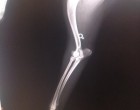

A rtg lapján: jobb oldali csípőcsont ficam és I tipusú Harris törés a distalis epiphyzisben, jobb oldali könyökízület ficam. A tüdőben enyhe beszűrődés látható, hasüregben folyadék nem látható, hólyag látszódik.Szív, tüdő rendben. A gyomra tele volt, a balesete előtt ehetett. A szája "csak" azért vérzett, mert a sokk következtében megharapta a száját, vagy a nyelvét.